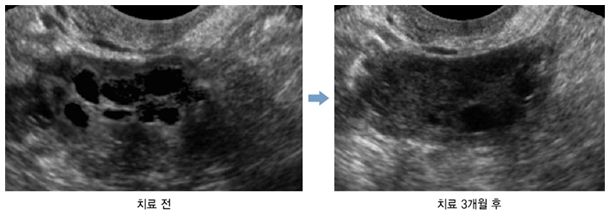

±è¿©Áø(°¡¸í, 26¼¼) ¾¾´Â ´Ù³¶¼º³­¼ÒÁõÈıºÀ» Áø´Ü¹Þ°í °­µ¿°æÈñ´ëÇѹ溴¿øÀ» ¹æ¹®Çß´Ù. 3°³¿ù°£ ÇÑ¾à º¹¿ë°ú ħ Ä¡·á¸¦ ÅëÇØ ¿ù°æ ÁֱⰡ 67ÀÏ¿¡¼­ 39ÀÏ·Î Á¤»óÈ­ °¨¼ÒÇß´Ù. ¶ÇÇÑ Æò¼Ò¿¡ ÀÚÁÖ °Þ´ø ¼ÒÈ­ºÒ·®°ú ¾îÁö·¯¿ò, ¸öÀÇ º×±â°¡ °¨¼ÒÇß´Ù. ±è ¾¾´Â °ñ¹Ý ÃÊÀ½ÆÄ °Ë»ç °á°ú, ¹è¶õÀÌ ¾È µÈ ä ³²¾ÆÀÖ´ø ¿ìÃø ³­¼ÒÀÇ ³­Æ÷ °³¼ö°¡ ÇöÀúÇÏ°Ô °¨¼ÒÇß´Ù.

´Ù³¶¼º³­¼ÒÁõÈıº ÇѹæÄ¡·á Ä¡·á Àü°ú ÈÄ